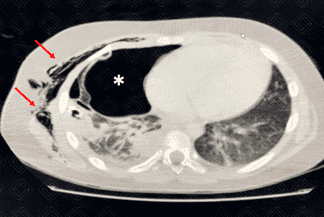

Descrição das figuras 1 e 2: Paciente em tratamento hospitalar de pneumonia comunitária complicada com derrame pleural. Apresenta piora clínica e laboratorial, com o padrão radiológico mantido na radiografia de tórax. Optou-se por realizar tomografia do tórax com contraste venoso para avaliar complicações.

Na tomografia, observamos a presença do dreno pleural (figura 1) adjacente à consolidação. Como complicação, observa-se pneumotórax à direita (asterisco - figura 2) e enfisema de partes moles ipsilateral (setas vermelhas - figura 2).